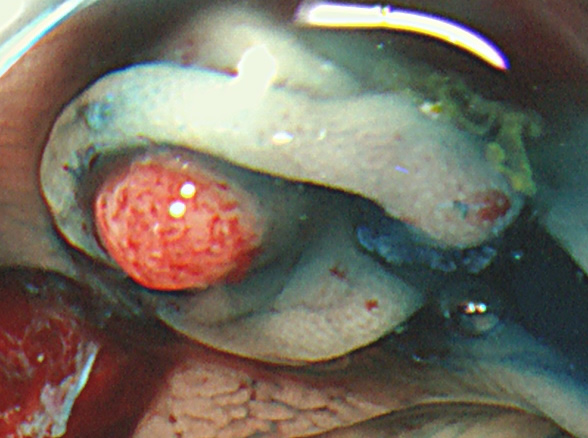

実際の「Extended Cold法」の模様を紹介します

しかしながら・・・いつも、このような綺麗な「目玉焼き」ができる訳ではありません。実際はスネアー(ワイヤー)が、うまくかからずに「分断」「分割」になったり、カンシ(ジャンボ・バイオプシー)を併用することも多いです。

患者さんの立場で言うなら、「ポリープ切除後の写真」をしっかり確認することが最も重要です。

重要なのはポリープではなく右の写真!!!